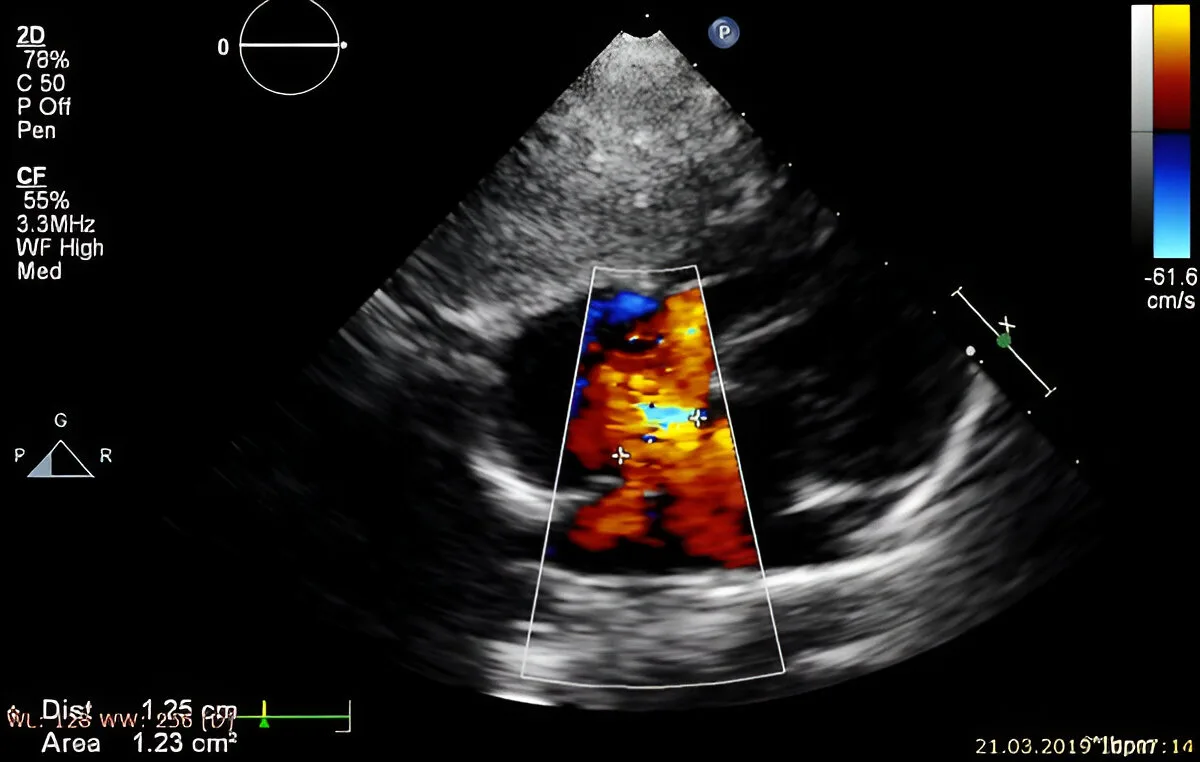

- ✓Color Doppler flow

The radiologist performs a structured examination, checking every major part of the developing baby for structural anomalies. [Image of fetal anomaly ultrasound scan] This includes detailed views of:

Doppler Assessment

If advised, blood flow through the umbilical cord, placenta, and fetal vessels is evaluated using Color Doppler. This ensures the baby is receiving adequate oxygen and nutrients.